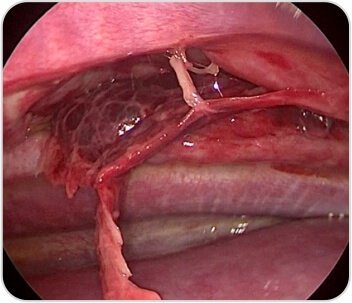

Intercostal hernia repaired with interrupted prolene sutures